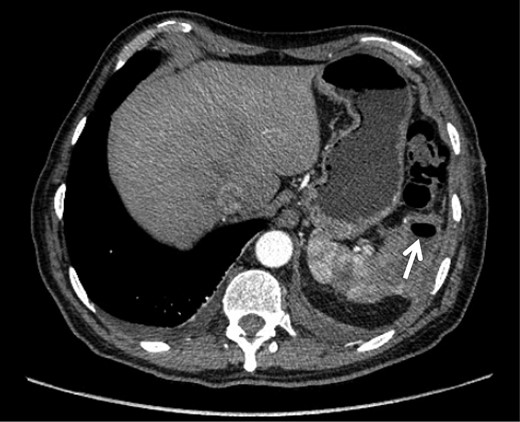

Intraoperative findings included extensive inflammation involving the inferior half of the spleen, the splenic flexure of the colon and the distal pancreas, as well as the abscess in question which contained approximately 10 cc of purulent material (Figs 3 and 4). The final surgical specimen included the entire spleen and the histologic report of pancreatic tissue compromised by the abscess. The patient was transferred to the surgical ICU for 24 hours. The following day, the blood cultures taken on admission grew an extended spectrum beta-lactamase producing Escherichia coli resistant to carbanemic agents and sensitive to tigecycline. The antibiotic regimen was modified accordingly, and after 7 days the patient was discharged symptom-free and with a plan to complete 15 days of tigecycline at home.

Splenic mass, inflammatory adherences from the major momentum to the spleen, colon and diaphragm.